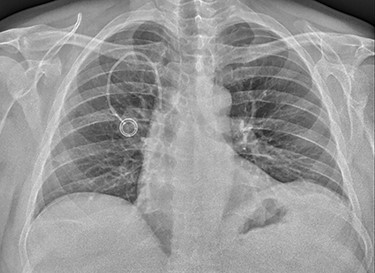

A 61-year-old male patient was diagnosed with inoperable stomach cancer. A TIVAD of the type Braun Celsite ST301® was inserted in the right subclavian vein for administration of chemotherapy. Location was confirmed by chest X-ray and the TIVAD was reported functioning with good backflow (Fig. 1). During initiation of the chemotherapy treatment, the TIVAD was reported malfunctioning. Contrast X-ray showed fibrin sheaths at the distal end of the catheter. An endovascular procedure was performed by an interventional radiologist and fibrin sheaths were mechanically removed with a snare (Fig. 2). Intraoperative X-ray with contrast showed normal contrast accumulation distal to the catheter tip and the patient received the first dose of chemotherapy. One month later the patient was hospitalized with bilateral pulmonary thromboembolism. The patient was treated with low-molecular-weight-heparin and discharged. The chemotherapy treatment continued as scheduled, with one pause due to a fracture of the right humerus after a fall. Occasionally, the TIVAD was malfunctioning and medication was administered using a peripheral venous catheter. During a planned pause in treatment, the patient sought hospital care due to worsening of his general condition. CT showed progress of malignancy and another round of chemotherapy was initiated and administrated using the TIVAD without any problems. Less than a week after, the patient reported feeling a tender swelling underneath his left foot. Ultrasound showed no DVT. The swelling and tenderness disappeared spontaneously, but the patient reported brief incidents of pain under his left foot. A CT scan was performed the next time the TIVAD did not function, showing that the distal 8 cm of the catheter was missing. The patient had no symptoms and reported no discomfort of any kind. The TIVAD was removed, confirming a fracture. A chest CT showed no foreign bodies. A full-body CT scan without contrast was performed, revealing the missing catheter part located at the level of the left knee (Figs 3 and 4). Vascular surgeons performed an endovascular procedure through the femoral vein assuming the catheter had embolized to the popliteal vein. Contrast examination revealed no catheter in the vein and another approach through the femoral artery was made, where contrast imaging shows that the catheter was, in fact, located in the popliteal artery (Fig. 5). The catheter, measuring 7.5 cm, was successfully removed with the use of a snare without any complications. The patient was discharged from hospital and referred to a diagnostic echocardiogram (Fig. 6). A bubble echocardiogram was performed to detect an atrial septal defect but was unsuccessful in doing so. For a final diagnosis, the patient was recommended a transesophageal echocardiogram, but as the diagnosis would not alter the course of treatment, the patient declined further examinations. Except for the reported episodes of pain and swelling of the left foot, the patient suffered no injury and finished his chemotherapy treatment.